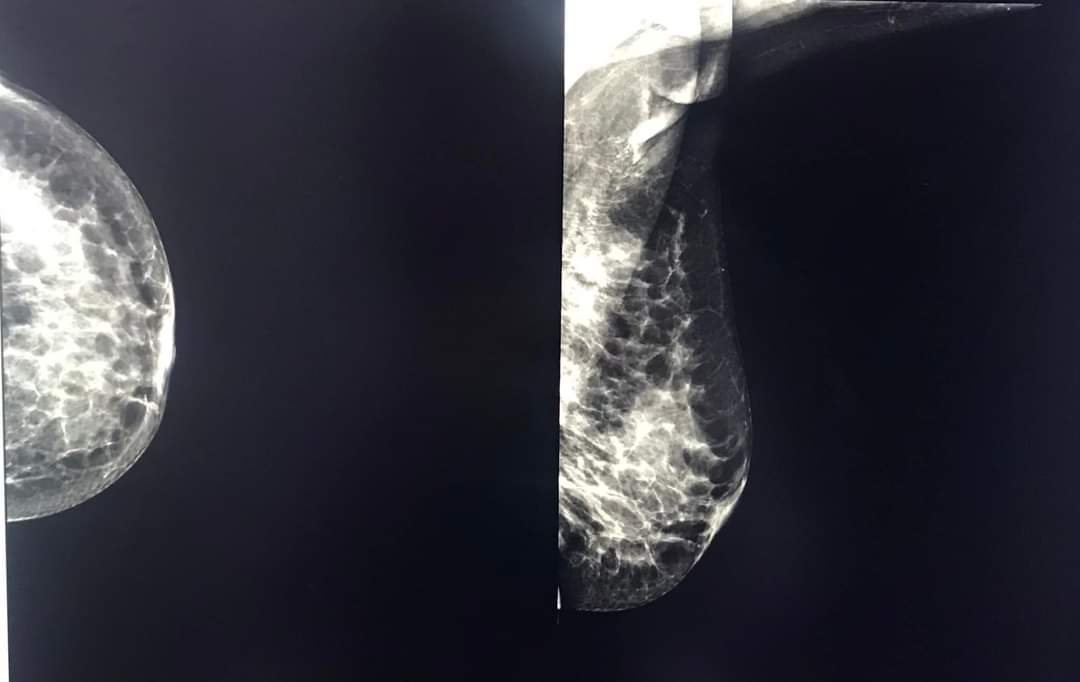

Mammogram

اشعة مامو كرام (Mammogram)للثدي الايمن والايسر Right,Left) (AP,Lateral)) لفتاة تشكو من الم و ورمه وزيادة في حجم الثدي (Fibroadenosis) تبين وجود ورم حميدو تليف الثدي ولا تحتاج لعمليه جراحيه